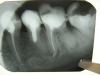

КТА Опубликовано 1 июля, 2011 Поделиться Опубликовано 1 июля, 2011 (изменено) коллеги, прошу совета. это до лечениядистальный канал не смогла пройти, медиальные дались легко. промыла парканом, кальций в каналы вот что получилось. пациентка пришла через сутки с болью....посоветуйте,как дальше быть. зуб ранее лечен рез.формалин.метод Изменено 1 июля, 2011 пользователем КТА Ссылка на комментарий

Scrabble Опубликовано 1 июля, 2011 Поделиться Опубликовано 1 июля, 2011 Наверно, вы слишком близко к фуркации ищете дистальные(или угол входа в каналы не тот). Судя по снимку, каналы проходимы. Ссылка на комментарий